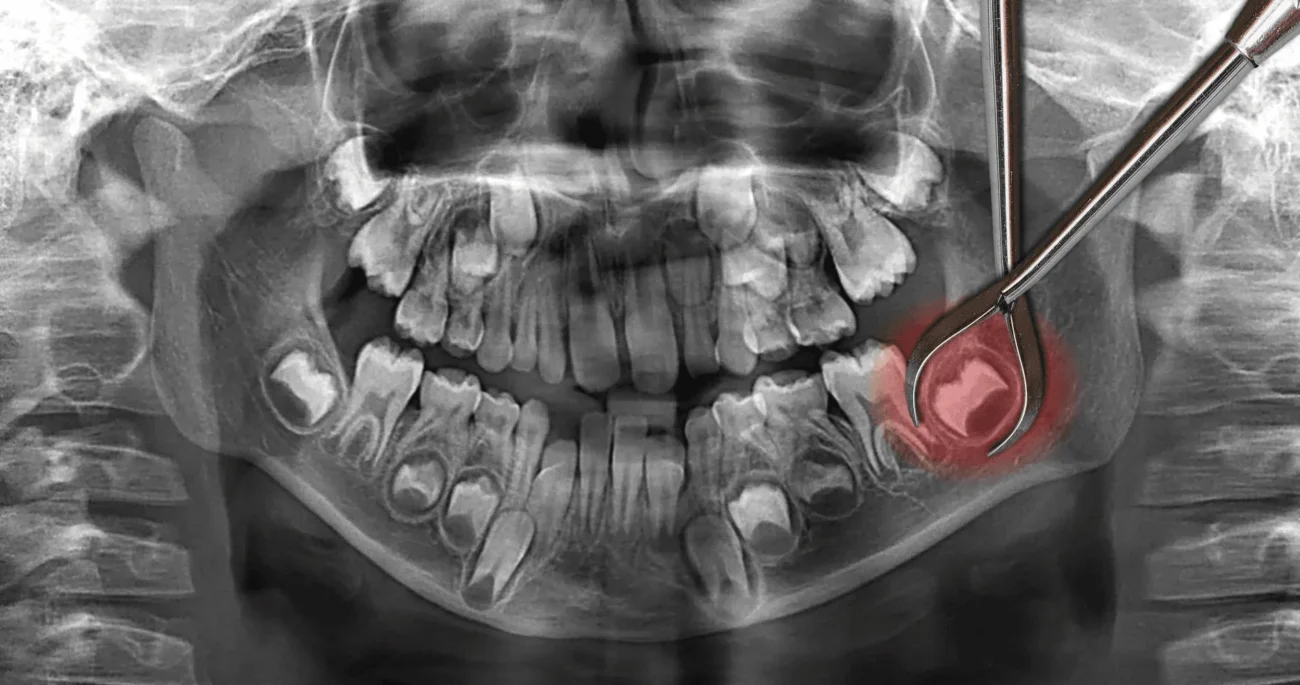

Some wisdom teeth become trapped in the jawbone and are only partially visible in the mouth; these are called impacted wisdom teeth. This situation can allow bacteria to enter around the tooth, leading to infections, toothache, swelling, and other oral diseases. Impacted wisdom teeth can also cause cysts or tumors that may damage the jawbone and surrounding teeth.

A complex (surgical) extraction is needed when the wisdom tooth is impacted—meaning it has not fully erupted into the mouth or is growing at an angle that prevents it from coming through the gum line properly.